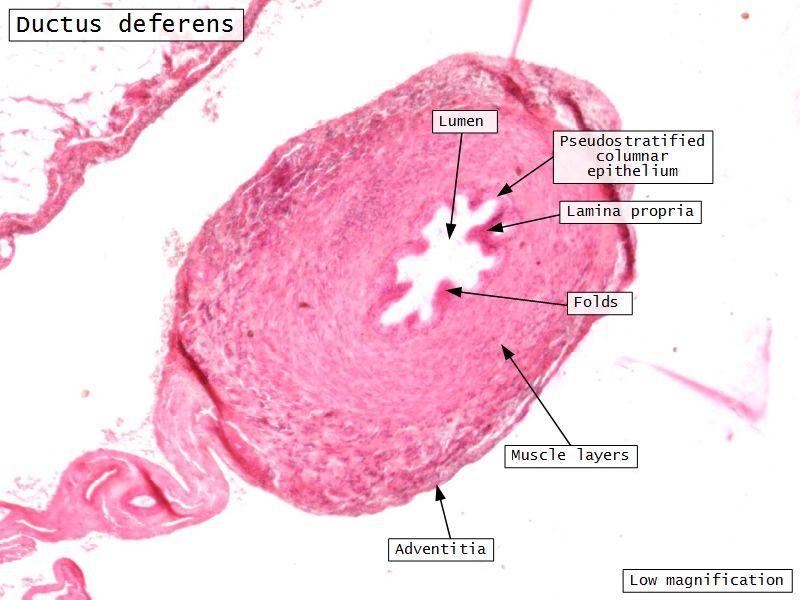

Ductus deferens

Also vas deferens

Ductus deferens

- Muscular duct with small lumen

- Lumen

- Pseudostratified columnar epithelium

- Stereocilia

- Fibroelastic lamina propria

- Muscle

- Inner longitudinal

- Middle circular

- Outer longitudinal

Ductus deferens

- Longitudinal folds in

- Epithelium

- Lamina propria

Ductus deferens

- Adventitia

- Loose CT with AVNL